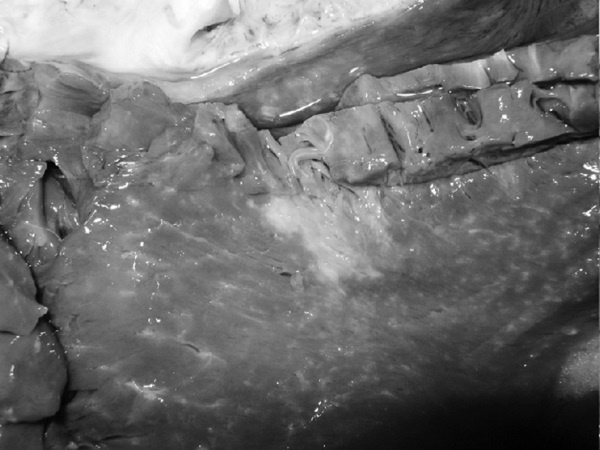

Последствия ОНМК: постинфарктные кисты головного мозга